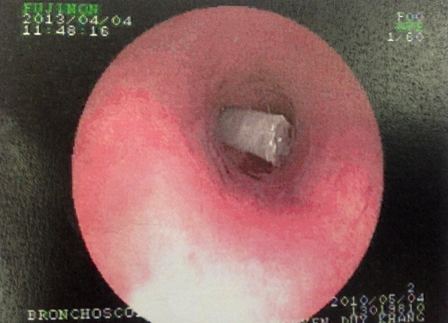

Chiếc béc thổi nằm chắn ngang trong phế quản bệnh nhi

Sau khi hội chẩn nhanh, bác sĩ quyết định điều trị bằng kháng sinh và kháng viêm tích cực để đẩy lùi tình trạng ho khò khè. Ngay sau đó, bệnh nhi được chỉ định nội soi kiểm tra phế quản. Đường đi của ống nội soi đã bị cản ngang bởi một mẫu nhựa trắng hình ống dính đầy đàm nhớt. Dị vật nhanh chóng được gắp ra ngoài và xác định đó là chiếc béc thổi gắn phía trong đầu kèn để tạo âm thanh khi thổi. Sau khi gắp được dị vật ra ngoài tình trạng của bé K. đã ổn định.